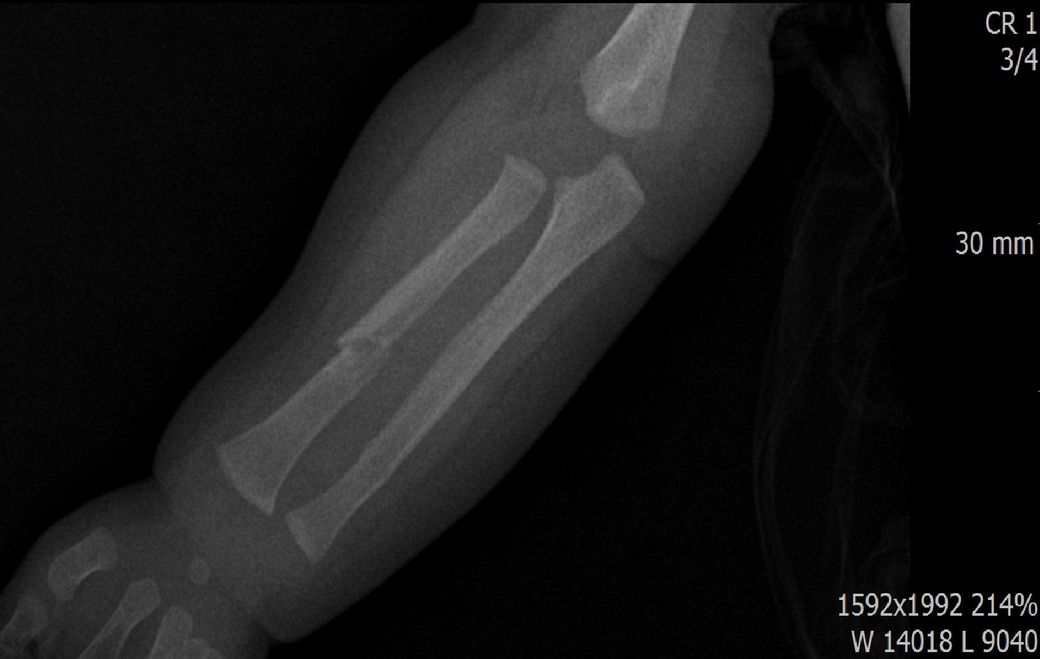

다름이 아니라, 첨부드린 엑스레이(X-ray) 사진처럼 골절 사실을 알게 되고 골절 발생 시점 대략적으로나마 추정시기를 파악하려고 문의 드리게 되었습니다

1) 3월 30일 촬영한 X-ray만으로 정확한 골절 시기를 100% 특정하는 데에는 한계가 있다는 점 충분히 인지하고 있기에 촬영날짜 기준으로 대략적으로 어느정도 시점에서 발생되었을 것으로 추측(ex 당일, 7~10일전, 7~14일 전, 10일 ~ 20일전, 14일 ~ 30일전 등등등)되는지 이해하고 싶습니다.

2) 미세한 금, 탈구 등이 있는 상태에서 정복 시도할 시 완전한 골절이 되고 붓기가 부어오를 수 있는지 여부가 궁금합니다.

• 4번 째 사진